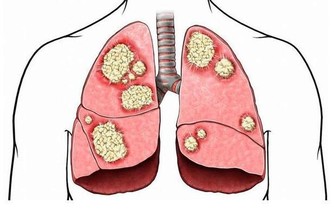

特別是對於那些身體虛弱或運動較少的人來說,過多的出汗會降低身體抵抗力,

讓人容易感冒,或出現腸胃、關節不適等症狀。